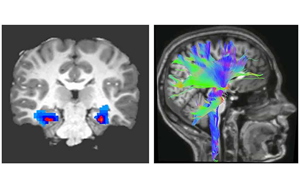

Nature Medicine:一種新的強(qiáng)迫癥神經(jīng)生物標(biāo)志物

貝勒醫(yī)學(xué)院和德克薩斯兒童醫(yī)院最近的一項(xiàng)研究確定了一種特定的神經(jīng)活動(dòng)模式,作為一種新的生物標(biāo)志物,可以準(zhǔn)確預(yù)測和監(jiān)測接受深部腦刺激(DBS)治療的強(qiáng)迫癥(OCD)患者的臨床狀態(tài),深部腦刺激是一種迅速出現(xiàn)的治療嚴(yán)重精神疾病的方法。